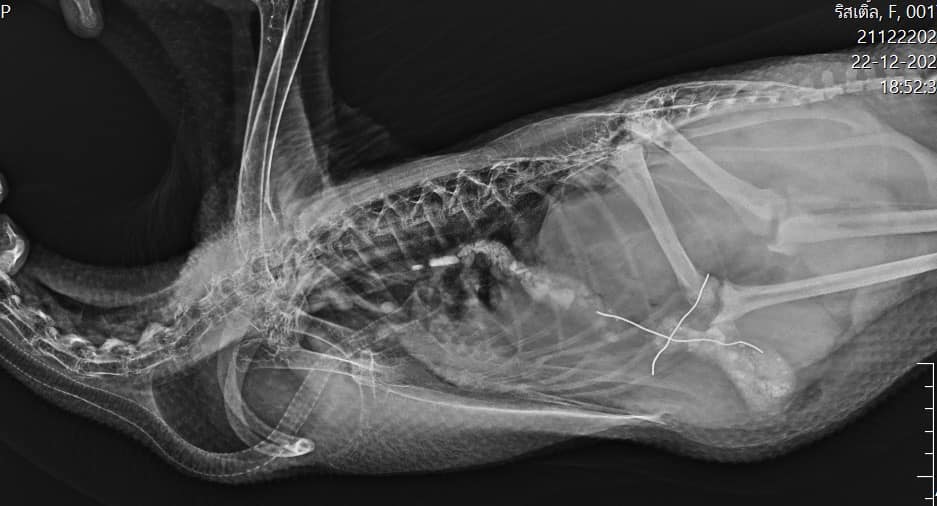

位於泰國暖武里府Tiwanon的動物醫院Panalai Veterinary Hospital,日前收治了一隻誤把電線吞下肚的白鵝,當時這隻貪吃P孩鵝已經完成鎮定麻醉,長脖子靠著枕頭、翅膀展開和雙腳伸直,乖乖躺在病床上了,而牠的腹部為了方便手術,也已先完成剃毛露出粉色的皮膚www